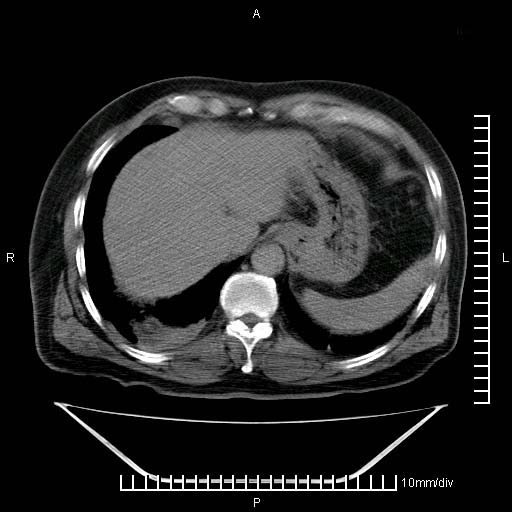

标题: CT25082:肝脏增强:男性,70岁 [打印本页]

标题: CT25082:肝脏增强:男性,70岁

患者以心脏疾病收住院,腹部无明显症状,b超查肝脏有占位。

牛眼征,中心坏死无强化,外缘强化,最外缘又见低密度,考虑转移,与脓肿鉴别

肝内多发转移瘤,右下肺炎症并少量胸水。胃壁增厚建议胃镜,胰尾部“病变”为肠管。

1)肝脏多发性转移瘤(不排除胰尾癌转移所致可能)。2)腹水。3)右侧少量胸腔积液。

ct25082 结果:转移瘤

外院mr结果:胰尾恶性占位。

肝多发低密度灶;轻度强化,较水密度高,考虑转移,不排除肝脓肿